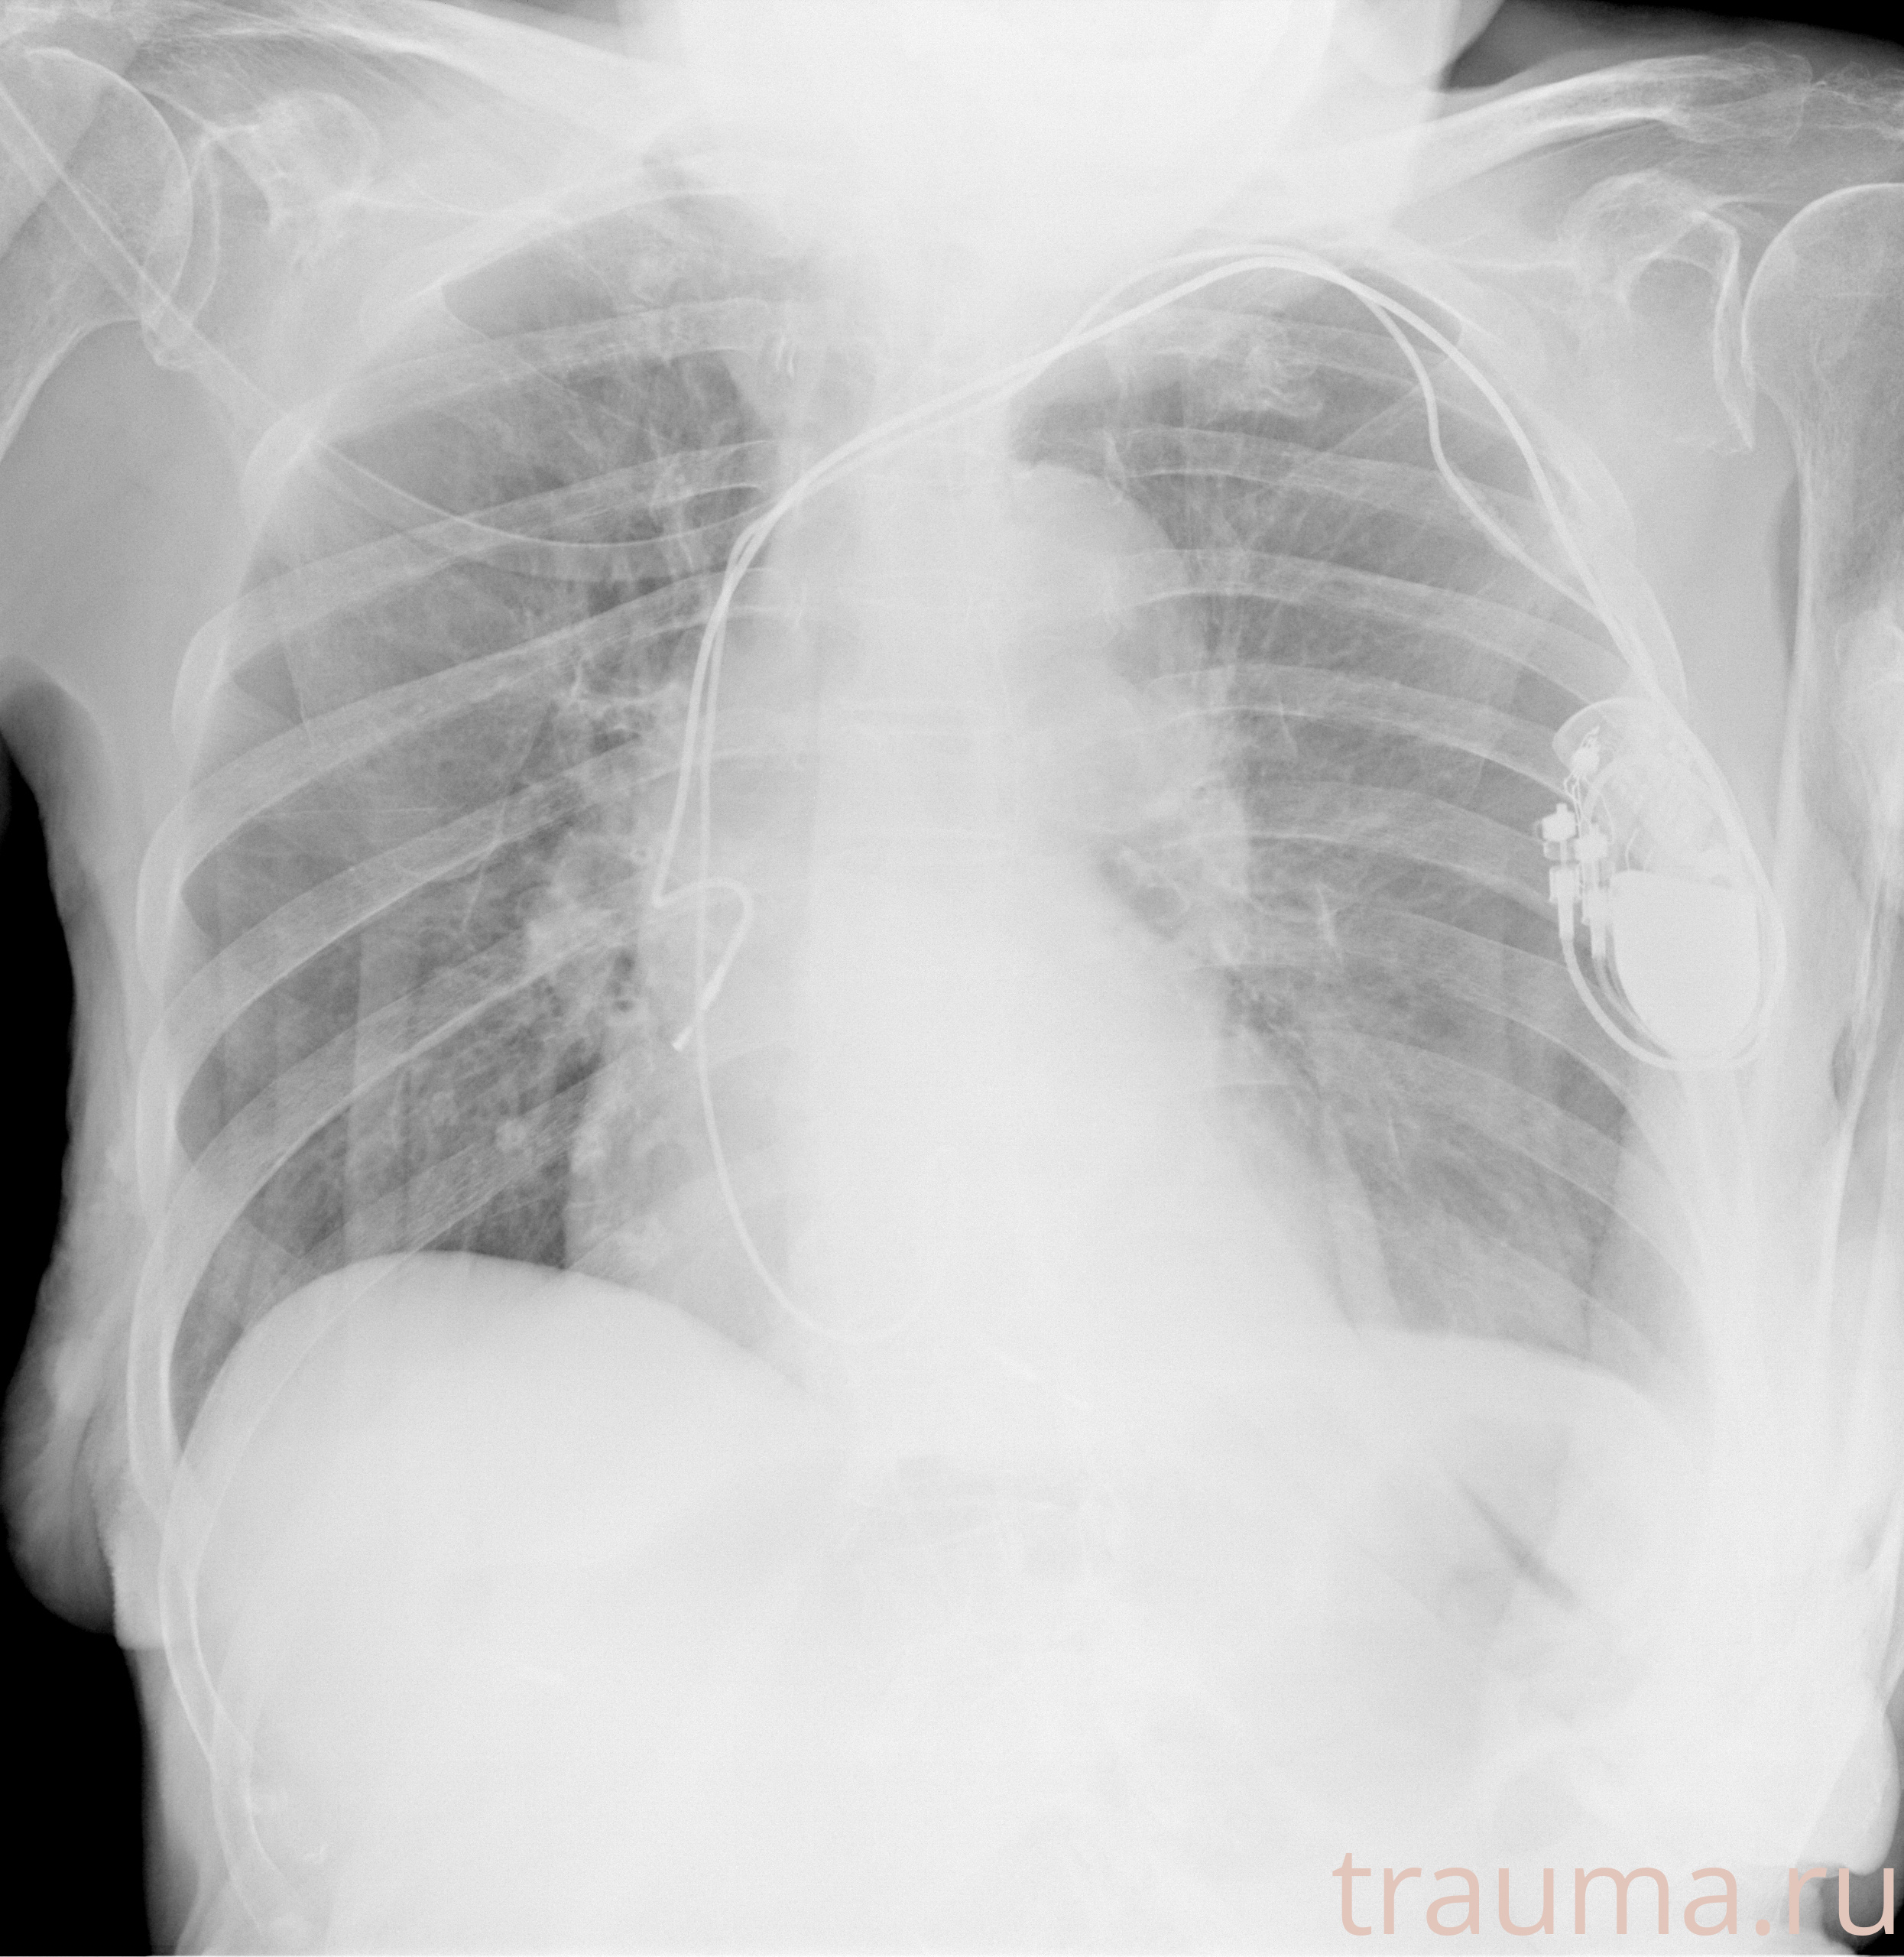

Рентгенограммы

Рентген на дому: по вашему адресу приезжает врач-рентгенолог, травматолог-ортопед с мобильным рентгеновским аппаратом, проводит диагностику травмы или заболевания, делает необходимые рентгенограммы, дает рекомендации по дальнейшему лечению. Получить качественные снимки в домашних условиях возможно благодаря уникальной методике, разработанной МосРентген Центром для института  Склифосовского

при переломе шейки бедра и пневмонии от компании МосРентген Центр - партнера Института имени Склифосовского